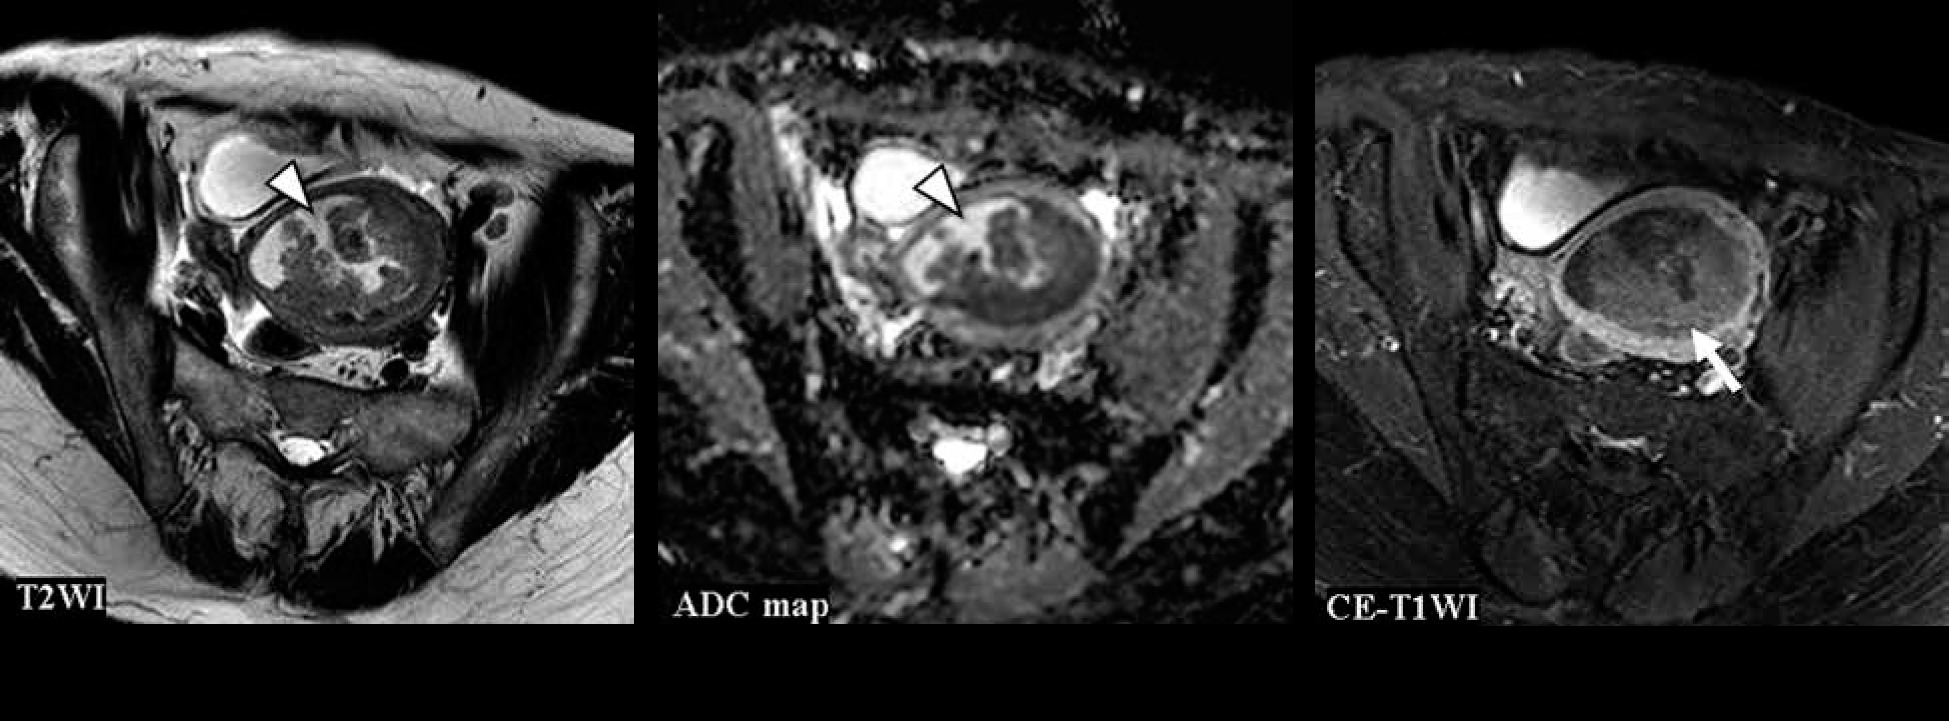

Figures 4-6 show the test images of this study with interpretations of the CNN model and the radiologists, including the confidence of the CNN model and the radiologists. Figure 4 is a typical CS case, where the CNN model and Reader 1 diagnosed CS on T2WI. On the other hand, only the CNN model could not diagnose CS on the ADC map, and all but Reader 2 diagnosed CS on CE-T1WI. Figure 5 presents a case of CS of a huge tumour with internal necrosis, where all but Reader 2 diagnosed CS on T2WI and ADC map, and only the CNN model diagnosed CS on CE-T1WI. Figure 6 shows a case of EC with haemorrhage in the endometrial cavity, where the CNN model diagnosed EC only on CE-T1WI.

Figure 4

A 72-year-old woman with carcinosarcoma showing heterologous differentiation of stage IVB. T2WI: the CNN model = CS (confidence; CS = 100.0%), Reader 1 = CS (confidence; CS = 100.0%), Reader 2 = EC (confidence; CS = 0.0%), Reader 3 = EC (confidence; CS = 40.0%). ADC map: the CNN model = EC (confidence; CS = 0.2%), Reader 1 = CS (confidence; CS = 80.0%), Reader 2 = CS (confidence; CS= 60.0%), Reader 3 = CS (confidence; CS = 80.0%). CE-T1WI: the CNN model = CS (confidence; CS = 100.0%), Reader 1 = CS (confidence; CS = 100.0%), Reader 2 = EC (confidence; CS = 20.0%), Reader 3 = CS (confidence; CS = 100.0%). The tumour showed relatively heterogeneous hyperintensities both on T2WI and ADC map (arrow heads); additionally, some parts were strongly enhanced on CE-T1WI (arrow), which were typical appearances of CS. However, it seemed difficult to distinguish it from EC associated with endometrial polyp. It may also have been difficult to distinguish from adenomyosis with the ADC map alone